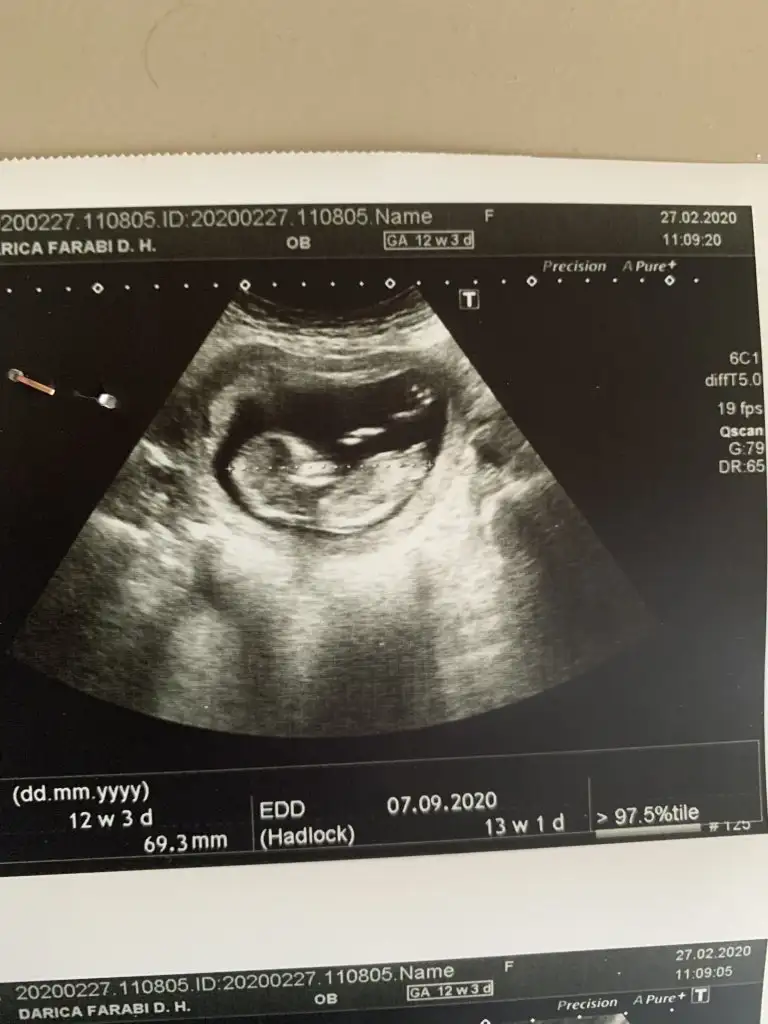

dr soylemeden siz gorun genital nub teorisi ( bebegin cinsiyeti)

Senin nubu çizdim cnm arkadaşında çizdim pipide vardı arkadaş pipi olsa söylemezmi deyince bende diğer 10 ve 11 haftasndaki tahminim devam dedim çok istiyordu pipiyi dr görmedi deyince ne kadar geç ögrenise dedim yoksa baya baya pipiydi çizdiğim usg 😊 seninkinide çizdim parelel görünüyor tabi pozisyonu nubu bazen değiştiyor. umarım 31 yanlış tahminim var arasında olmazsın onlar beni yanıtan usgler 😊

teşekkürler doktor erkek gibi ama emin değilim dedi 1 ay sonra kontrol inş. geri dönüş yapacağım iyi akşamlar.